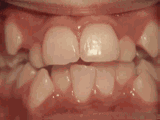

牙列拥挤,牙槽骨过窄,牙齿没有足够空间,只好前后左右高低上下乱长,经过矫正后的牙齿是这样的~